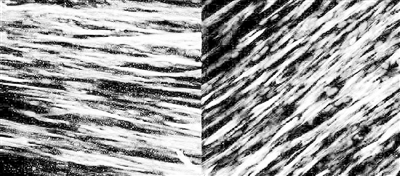

图上染色显示,经一周培养后,人工动脉能产生收缩蛋白(左)和肌钙蛋白(右),这两种分子能让动脉收缩舒张,对外部刺激产生反应。

动脉壁有多层细胞,内皮细胞在最里面,与血液循环相互作用,间层由平滑肌细胞构成,帮助控制血流和血压。这两层通过一套化学信号来沟通,控制着血管系统对药物、体育锻炼等外部刺激的反应。研究团队造出了包含两层细胞的人工动脉,并证明了这两层之间能沟通,正常发挥功能。